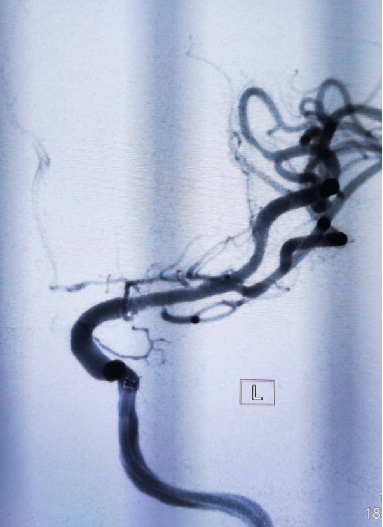

入院影像检查

导丝怎么扩【载药时代 球扩天下】NOVA DES®颅内药物洗脱支架在大脑中动脉重度狭窄中的应用两例!_https://www.jmylbn.com_新闻资讯_第16张

导丝怎么扩【载药时代 球扩天下】NOVA DES®颅内药物洗脱支架在大脑中动脉重度狭窄中的应用两例!_https://www.jmylbn.com_新闻资讯_第17张

重要影像结论DSA:左侧大脑中动脉M1段重度狭窄。